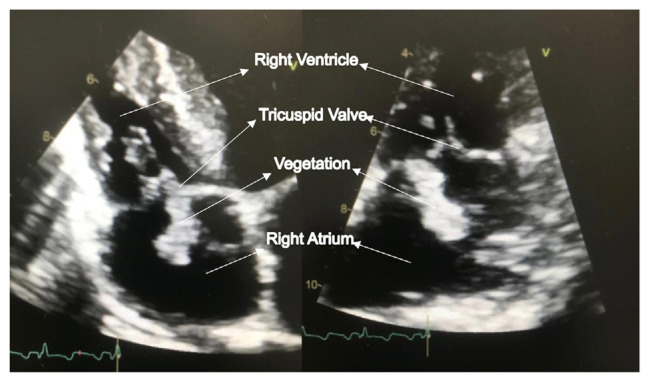

Fungal endocarditis (FE) is a rare yet life-threatening condition, especially in hemodialysis (HD) patients with indwelling long-term catheters. Symptoms often overlap with non-fungal infective endocarditis, making diagnosis difficult. As FE incidence increases, healthcare providers face challenges in diagnosing and managing this severe condition. Early suspicion of FE is crucial for patients with long-term catheters. We reported a 23-year-old male with end-stage renal disease (ESRD) on HD that developed FE affecting the tricuspid valve, requiring valve replacement and anti-fungal medication. Despite these interventions, he had recurrent Candida prosthetic endocarditis (CPE). Currently, he is receiving anti-fungal medication, with plans for a third surgery.